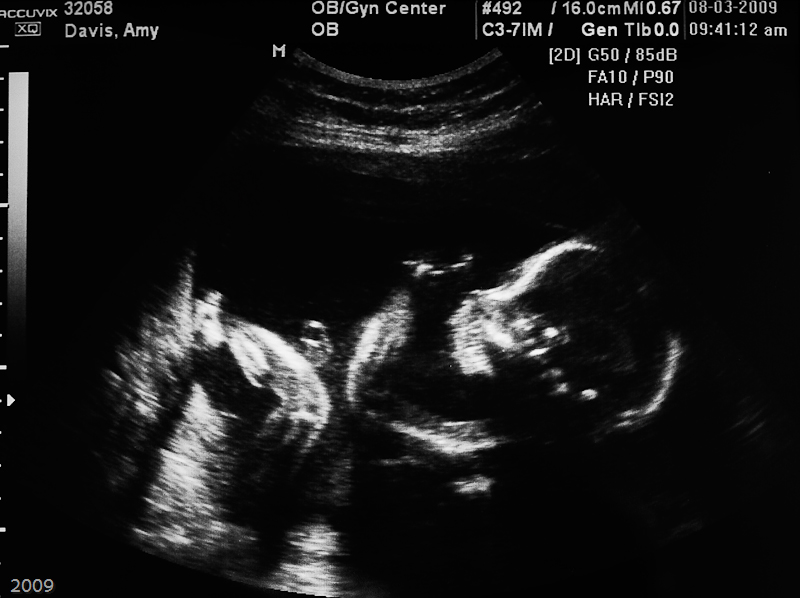

It's a Boy!

20 Week Ultrasounds

20 Week Ultrasounds, where we found out it's a boy!

Baby at 20 weeks